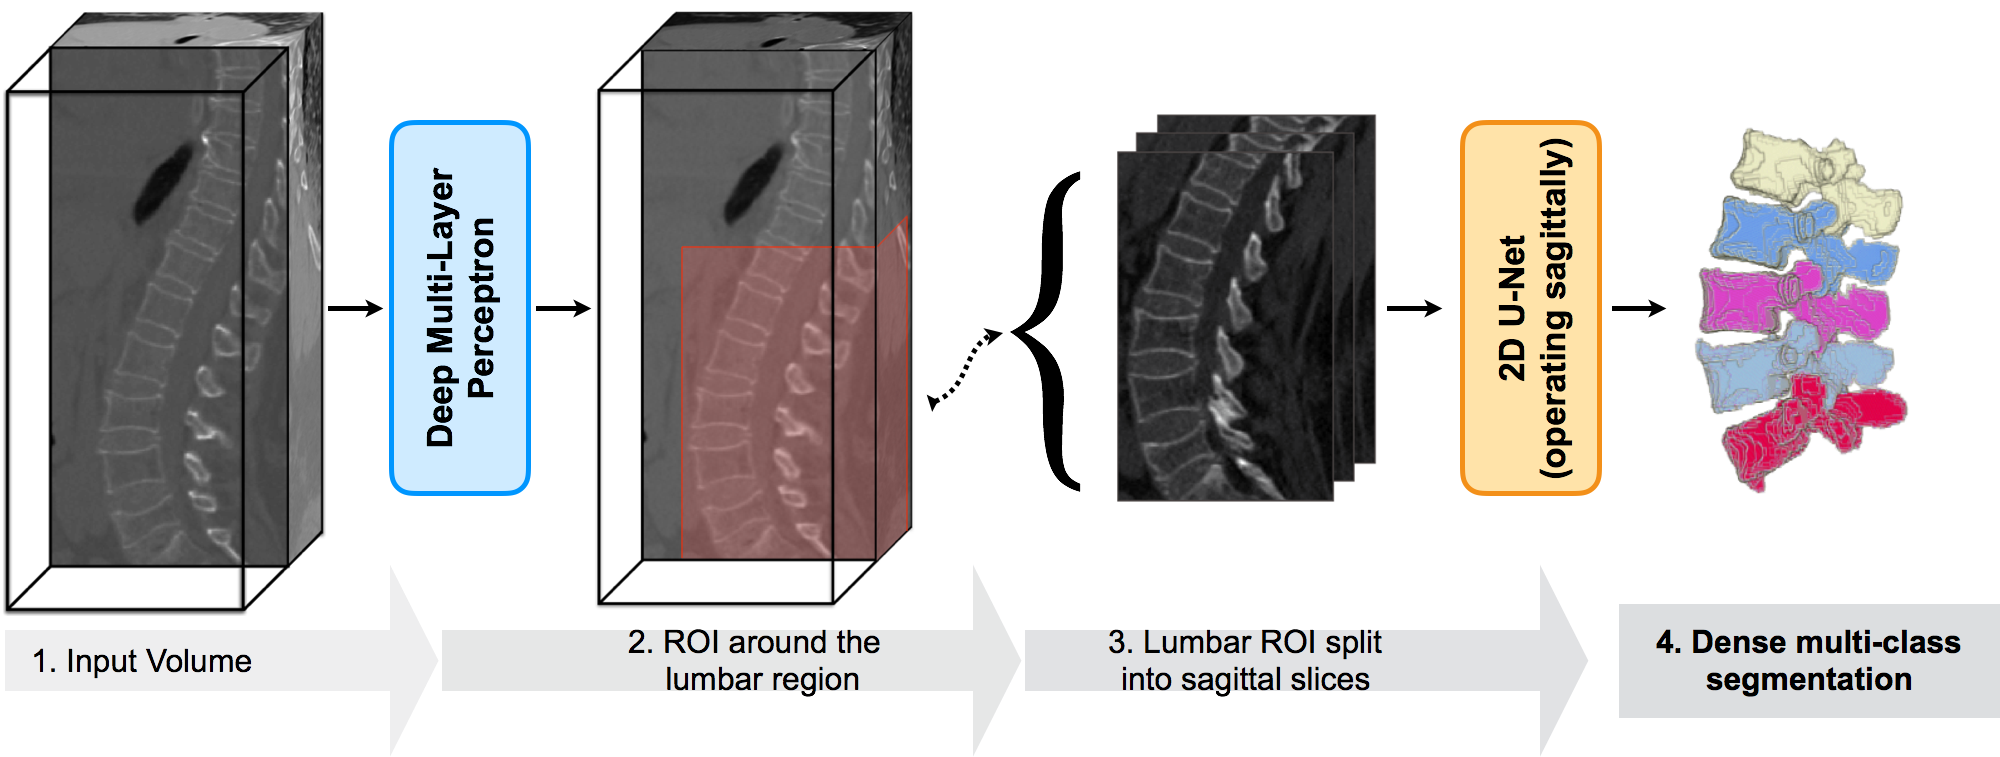

In this work, we propose an approach that segments and simultaneously labels the the lumbar vertebrae using deep neural networks. Given a CT scan volume of an arbitrary FOV, our approach performs a multi-class segmentation over five classes corresponding to the five lumbar vertebrae (L1 to L5) and a background class. This is done in a two-staged approach: (1) Localise the lumbar region, and (2) Segment the localised lumbar vertebrae in to their respective classes. Both the stages are elaborated in detail in section 2. Figure 1 gives a schematic overview of our approach. We use the dataset released as part of the xVertSeg challenge in MICCAI 2016 to test the performance of our approach. We are the first to attempt this challenge, and achieve a mean Dice coefficient upwards of 90% on both the training and the test set. Section 3 contains the implementation and experimental details.

2.1 Lumbar localisation

When compared to typical binary segmentation, multi-class segmentation is inherently difficult due to a more complex representation that is to be learnt. Moreover, the appearance of adjacent vertebrae are highly correlated. Thus, instead of directly attempting the segmentation problem on the entire scan, we choose to restrict our attention to a restricted region of interest - the lumbar region.

2.1.1 Non-linear Regression using deep neural network

We pose the localisation of the lumbar region as a regression problem, and employ a five-layered perceptron with ReLU (rectified linear unit) activation as a regressor. It is trained on contextual, intensity-dependant features that encode long-range spatial information, as in [5], and regresses on the location of the six planes that define a bounding box. An lenght feature, can be constructed at the voxel location of as below:

| (1) |

where , is the mean intensity of the 3D image region lying inside a cuboid that is centered at a certain offset from the voxel at . The cuboid’s offset and the dimension are generated randomly for construction of a feature. Given these features, each of them corresponding to a voxel location, the regressor should predict the region-of-interest, or a bounding box around the lumbar region.

In a simple set-up, a bounding box can be defined by six planes: , the smallest -coordinate, , the largest -coordinate, and their and equivalents. These are refereed to as the bounding planes. Given the contextual information through the feature , a six-length vector encoding the voxel’s location relative the bounding planes is learnt, as below:

| (2) |

2.1.2 Estimation of the lumbar bounding box

Each pass through the regressor using a feature corresponding to a certain voxel predicts the locations of the bounding planes with respect to that voxel. In order to speed-up the feature generation procedure without loss of useful information, only the significant voxels are considered for feature extraction. For this purpose, the voxels from the response of a Canny’s edge detector are used for feature extraction. Thus, every significant voxel votes for a prospective bounding box of which the most representative bounding box is chosen. Figure 2 shows a few examples of the localised lumbar regions.

2.2 Multi-class Segmentation

Once the lumbar region is successfully identified, the FOV is restricted, enabling a human to effectively identify the vertebrae, based on certain key points such as the sacrum, number of vertebrae in the FOV etc. We make use of a deep convolutional network to learn such key points on its own in order to segment and annotate the lumbar vertebrae.

2.2.1 Fully-convolutional network for multi-class segmentation

This is the segmentation of the vertebrae is carried out by a fully convolutional network (FCN). We rely on the 2D U-net [10], but implement an architecture that one level deeper, i.e., six more convolutional layers, three each in the contracting and expanding path, joined by one additional downsampling and up-convolutional layers, and works on sagittal slices from the localised lumbar region. The motivation for a deeper network is to adapt it towards multi-label classification of vertebrae by increasing the receptive field of the coarsest level. The receptive field of our FCN ( 270270 pixel2 or 2727) covers at least two vertebrae when working at isotropic resolution. Such a receptive field will force the network to learn the sequence of vertebrae in pairs, L1-L2, L2-L3 etc., so that the sequence of the annotations is always in order.

2.2.2 Pre-training

It is a common practice to pre-train a network for one purpose and use it as an initialisation for another network attempting a related yet more-complex task. For example, Long et al. [11] use the state-of-art recognition networks (VGG-16 etc.) as initialisation for the task of segmentation. On a similar footing, a network trained for binary segmentation of lumbar spine (spine vs. background) is employed as an initialisation for the multi-class segmentation. This alleviates the shortcoming of the limited data at our disposal to train a very deep network for the relatively complex task of multi-class segmentation.

2.2.3 ROI Augmentation

Another key concept in our segmentation routine is the ROI augmentation step. However, the localisations are not uniform as shown in figure 2. There could either be non-lumbar vertebrae showing up in the sagittal slices (usually T11 and T12 in our experiments), or part of the lumbar region could be missing (usually L1 in our experiments). The high correlation in the appearance of the vertebrae makes this problem detrimental. Therefore, in addition to augmenting the sagittal slices using elastic and rigid transformations, we also augment based on varying bounding boxes sizes. Let be the dimension of the lumbar bounding box obtained from the localisation stage. We augment the sagittal slices from bounding box by randomly choosing a so that the sagittal slice dimensions vary between and . This makes the segmentation network robust to improper lumbar localisations.